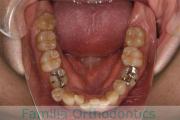

No.22V-029

- 叢生

- 上顎前突

- 19歳

- 男性

- 上:

- 8448

- 下:

- 主な使用装置:

- FEA 022

- 治療にかかった費用:

- 92万円

でこぼこを治したいということで来院されました。上下左右から親知らずも第一小臼歯も抜歯が必要で、歯科矯正アンカースクリューを併用して大臼歯を後ろに引っ張りながらの治療でした。3年弱、35回程度の通院が必要でした。

叢生が著しく、後戻りのリスクがあります。またアンカースクリューが必須のため、もしもスクリューが安定しないと、治療が難しく長くなってしまう恐れがありましたが、幸い脱落は見られませんでした。